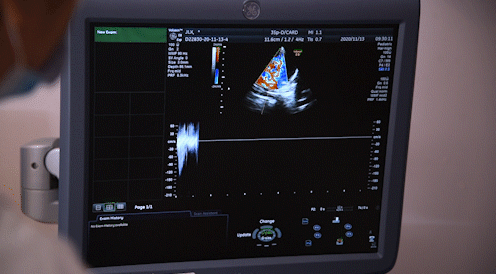

胎儿心脏彩超是胎儿心脏产前超声初步检查,主要采用超声成像技术及彩色多普勒血流成像技术,观察胎儿心脏的大体形态结构,以便对大部分胎儿先天性心血管结构畸形进行可靠的产前筛查和评估。